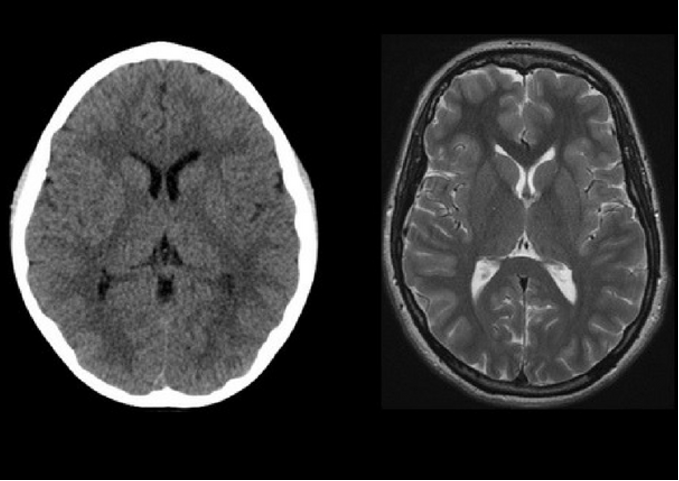

Which picture is the MRI?

What are you looking for on the rapid head CT during a stroke alert?

What is bleeding, hyperdensity to suggest ischemic stroke, or loss of grey-white matter differentiation?

What finding are you looking for on MRI during an MS evaluation?